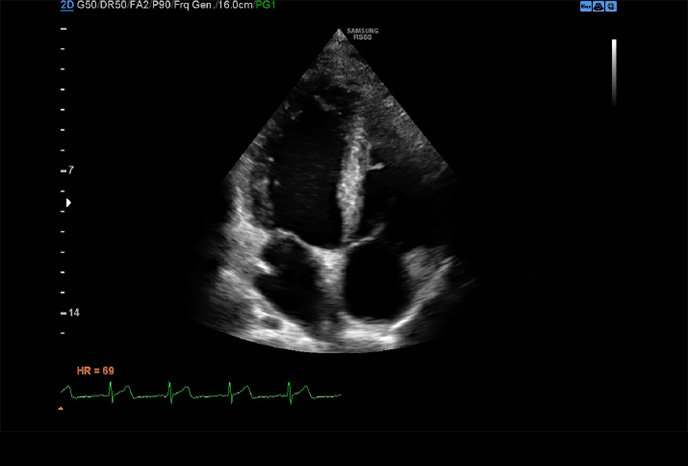

Strain+

Strain + je kvantitativní nástroj pro měření celkového a segmentového pohybu stěny levé komory (LV). Ve Strain + se na obrazovce zobrazují tři standardní pohledy levé komory a Bull's Eye pro snadné a rychlé vyhodnocení funkce LV.